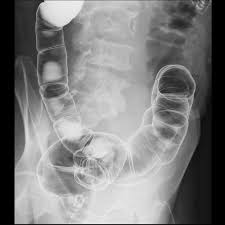

대장 선종의 진단

대장 선종을 가장 정확하게 진단할 수 있는 방법은 대장내시경 검사입니다. 대장 전체를 살펴볼 수 있으며, 선종이 발견되면 동시에 조직 생검이나 절제술을 시행할 수 있습니다. 내시경 중 발견되는 선종은 크기와 위치에 따라 적절한 방식으로 제거되고, 병리검사를 통해 이형성의 정도가 판단됩니다.